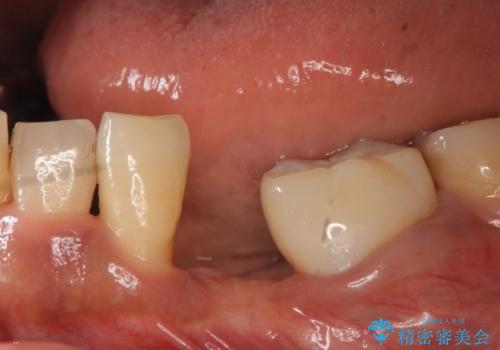

- 左下の歯並びが悪く、左側で物が咬みにくいので診て欲しいといらっしゃった方の症例です。

歯列矯正は御希望されなかったため左下4、5番目の歯を抜歯し、インプラントによる欠損補綴を行いました。

カスタムアバットメントについて

カスタムアバットメントは患者様それぞれの歯茎に合わせて製作されたオーダーメイドのアバットメントです。

既製のアバットメントに比べ適合がよく、高い清掃性を誇ります。